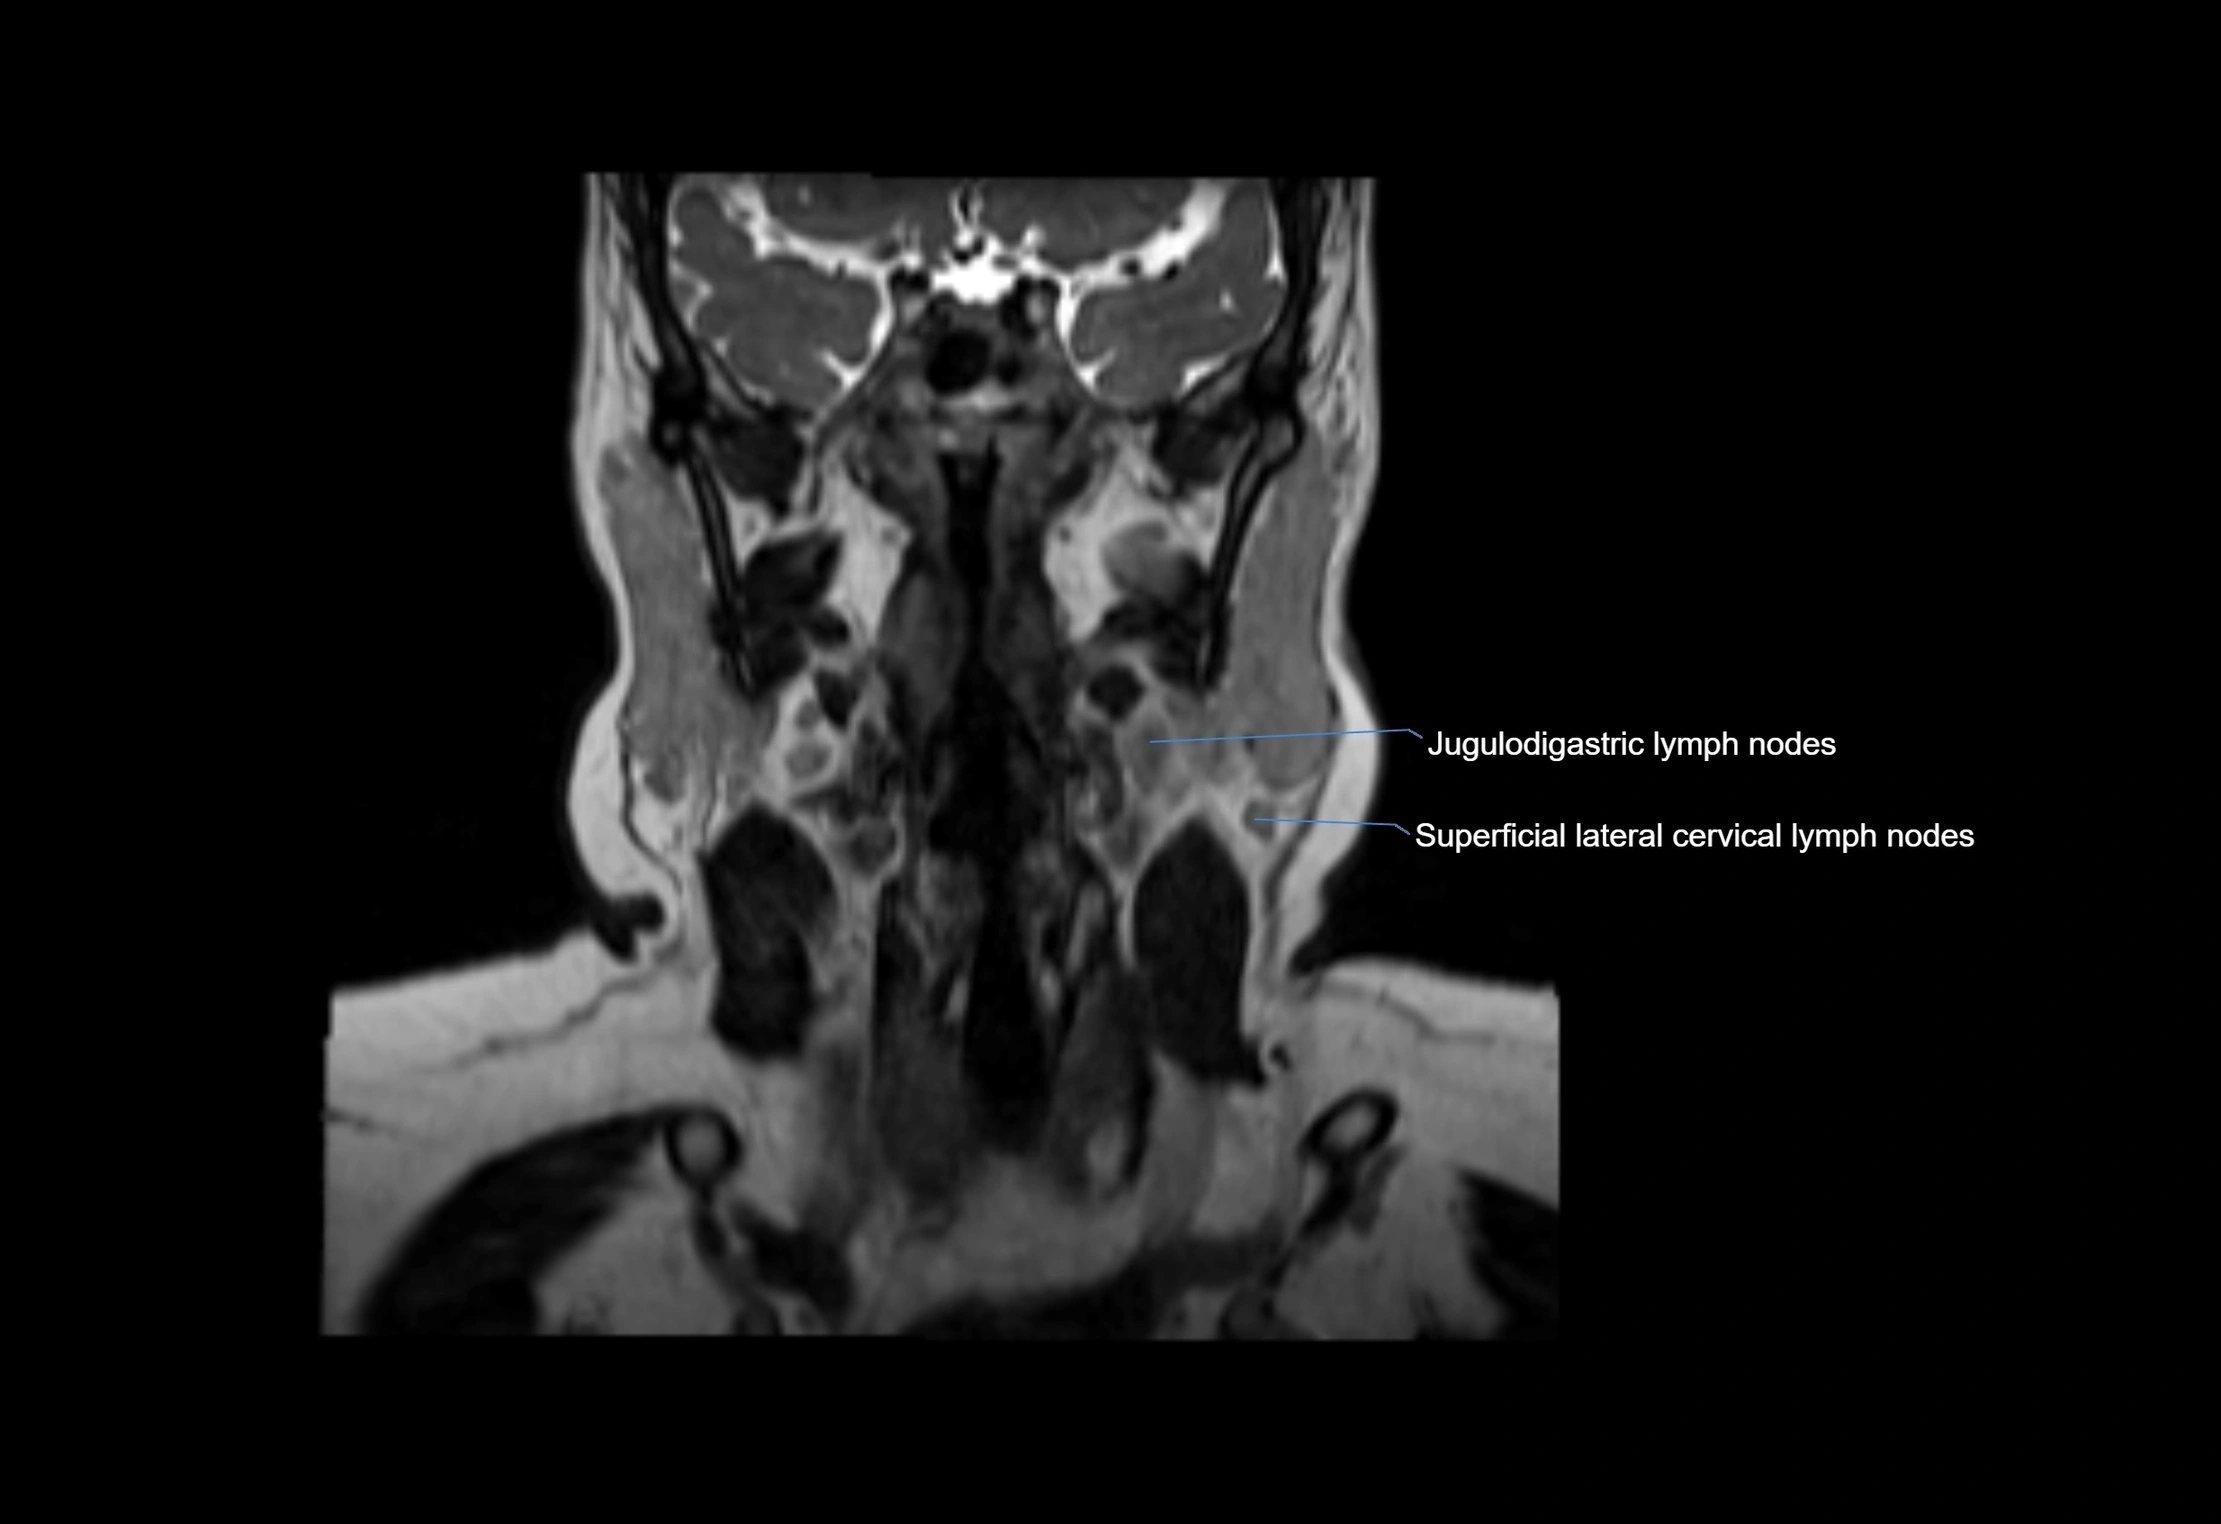

MRI Appearance

T1-weighted images:

• Normal accessory nodes appear as small, oval hypointense to intermediate signal structures within subcutaneous fat

• Surrounded by hyperintense fat, enhancing contrast for visualization

• Pathological nodes may appear enlarged or rounded, sometimes with cortical thickening

T2-weighted images:

• Nodes show intermediate signal, with surrounding fat bright

• Useful for detecting edema, inflammation, or infiltration

• Fatty hilum may appear slightly hyperintense relative to cortex

MRI images

image